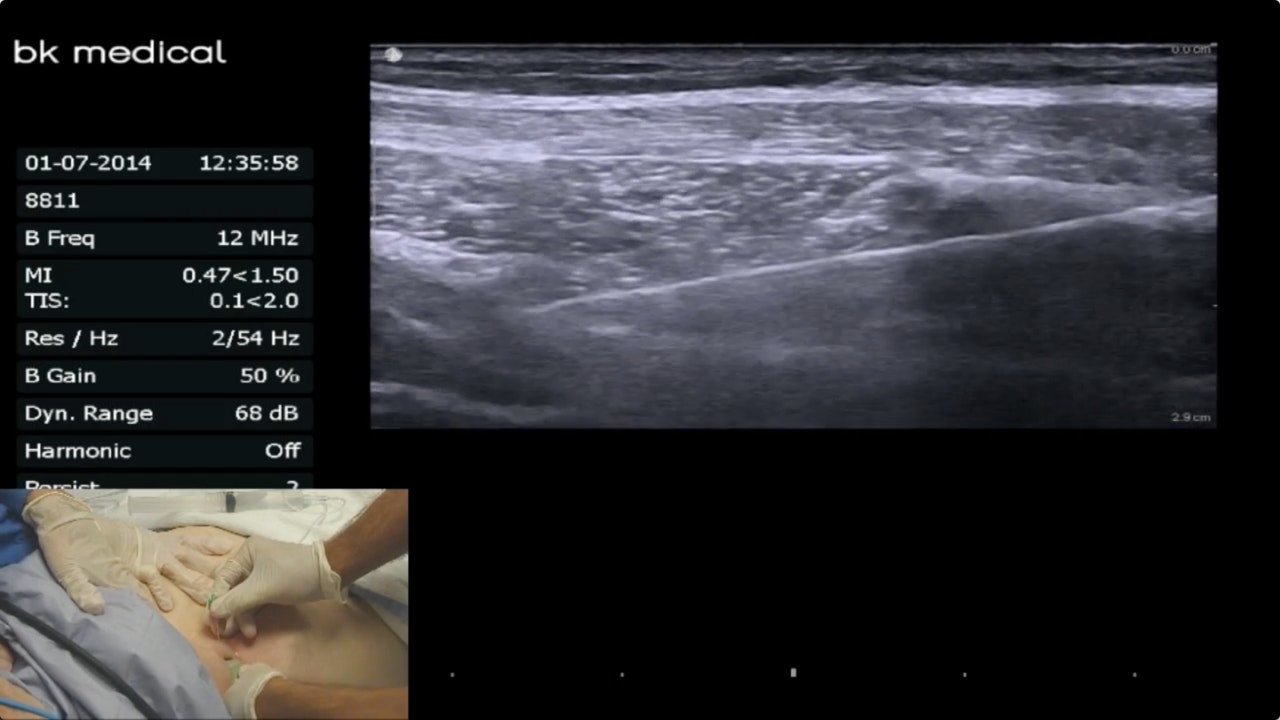

The TAP block. (A) The linear transducer was placed transversely on the What Is A Tap Block After C Section Tap block reduces pain, prolongs the duration of analgesia and decreases supplemental opioid consumption when used for multimodal analgesia for pain relief after caesarean. During the initial hours after the cesarean section, the implementation of the tap block procedure exhibited a notable improvement. The transversus abdominis plane (tap) block is a fascial plane block performed by injecting local anesthetic in. What Is A Tap Block After C Section.

The UltrasoundGuided TAP Block YouTube What Is A Tap Block After C Section The transverse abdominis plane (tap) block, a regional block provides effective analgesia after lower abdominal surgeries if used as part of. During the initial hours after the cesarean section, the implementation of the tap block procedure exhibited a notable improvement. The transversus abdominis plane (tap) block is a field block that provides postoperative analgesia for abdominal surgery. Its analgesic utility. What Is A Tap Block After C Section.

Process of TAP block as seen on ultrasound examination Download What Is A Tap Block After C Section The transversus abdominis plane (tap) block is a field block that provides postoperative analgesia for abdominal surgery. The transverse abdominis plane (tap) block, a regional block provides effective analgesia after lower abdominal surgeries if used as part of. During the initial hours after the cesarean section, the implementation of the tap block procedure exhibited a notable improvement. Morphine consumption in. What Is A Tap Block After C Section.